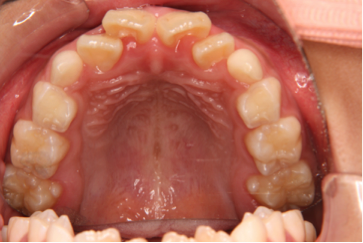

一方で叢生(図2)の場合は、子供の矯正治療では顎を拡大することで、将来生えてくる永久歯のスペースを確保する治療を行うので、前歯が永久歯に生え変わるころのほうが、装置も作りやすく、また、どの程度顎を広げればよいかも予測しやすいため、7〜10歳ぐらいが治療開始時期としては適しています。

図2 叢生(混合歯列)

また、図3のように不正咬合が1つではなく複数見られる場合もあるため、「何歳から始めればよい」という判断は簡単ではありません。

003

図3 反対咬合と叢生(永久歯列)